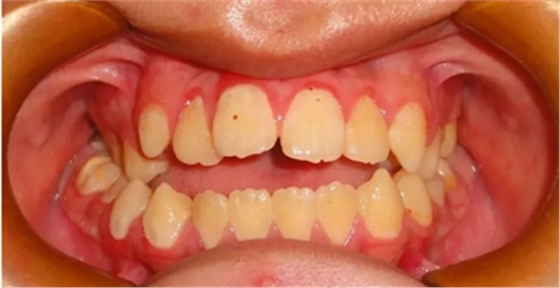

03 牙列擁擠

因虎牙特別突出、牙齒層次不齊前來就診,該如何避免?